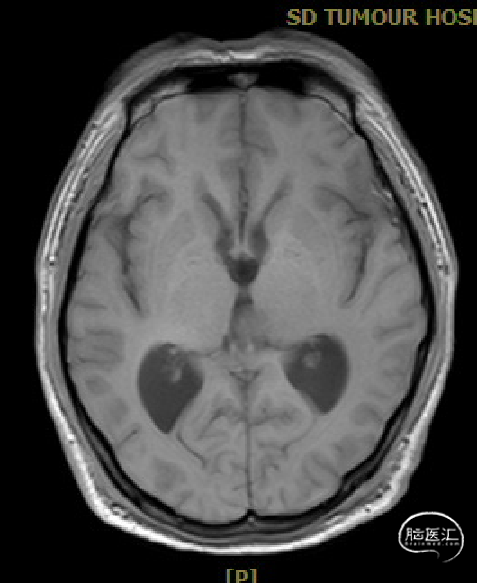

患者5年前无明显诱因出现阵发性头晕,无明显头痛、恶心呕吐等不适,开始未予重视,2022-7-19出现头晕加重,伴视力下降,遂于2022-7-24在当地医院行颅脑MRI提示:松果体区肿瘤伴梗阻性脑积水。

于该院在2022-7-27全麻下行松果体区病灶部分切除活检+神经内镜下第三脑室底造瘘术,术后由于取出肿瘤组织少,未能明确病理结果。患者术后恢复顺利,为进一步治疗就诊于我院。

入院检查

松果体区占位,胶质瘤?生殖细胞肿瘤?

脑积水

脑梗死